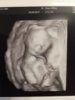

Gratulacje z udanej wizyty [emoji4]My już po wizycie, Wszystko w jak najlepszym porządku [emoji16] Coraz bardziej lubię tego mojego lekarza, taki serdeczny i cierpliwy [emoji4]

A u mnie co wychodzi bo nie ogarniam tej teorii i nie widze tej kosmowki